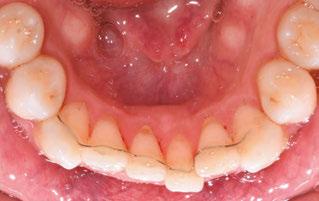

Figure 3: Initial right buccal

This case involves a 13-year-old female patient with a complex malocclusion that includes multiple dental and skeletal issues. During the initial consultation, clinical evaluation showed severe maxillary crowding along with generalized spacing in the mandibular arch. The patient’s occlusal relationships were asymmetric, with a Class I molar relationship on the right side and a Class II molar relationship on the left. Notably, an anterior crossbite was observed, further complicated by a narrow, V-shaped maxillary arch — a common presentation that often exacerbates anterior-posterior discrepancies and limits functional occlusion. The patient also demonstrated poor oral hygiene, which is a key indicator of an indirect bonding system that does not reduce excess flash. ODB is superior in flash reduction, by being able to remove excess adhesive from three sides of the bracket instead of competitors who only remove adhesive from one side of the bracket. The presence of adhesive around brackets contributes to surface roughness which leads to plaque accumulation.1 Flash reduction will be very important for every patient’s orthodontic success (Figures 1-3).